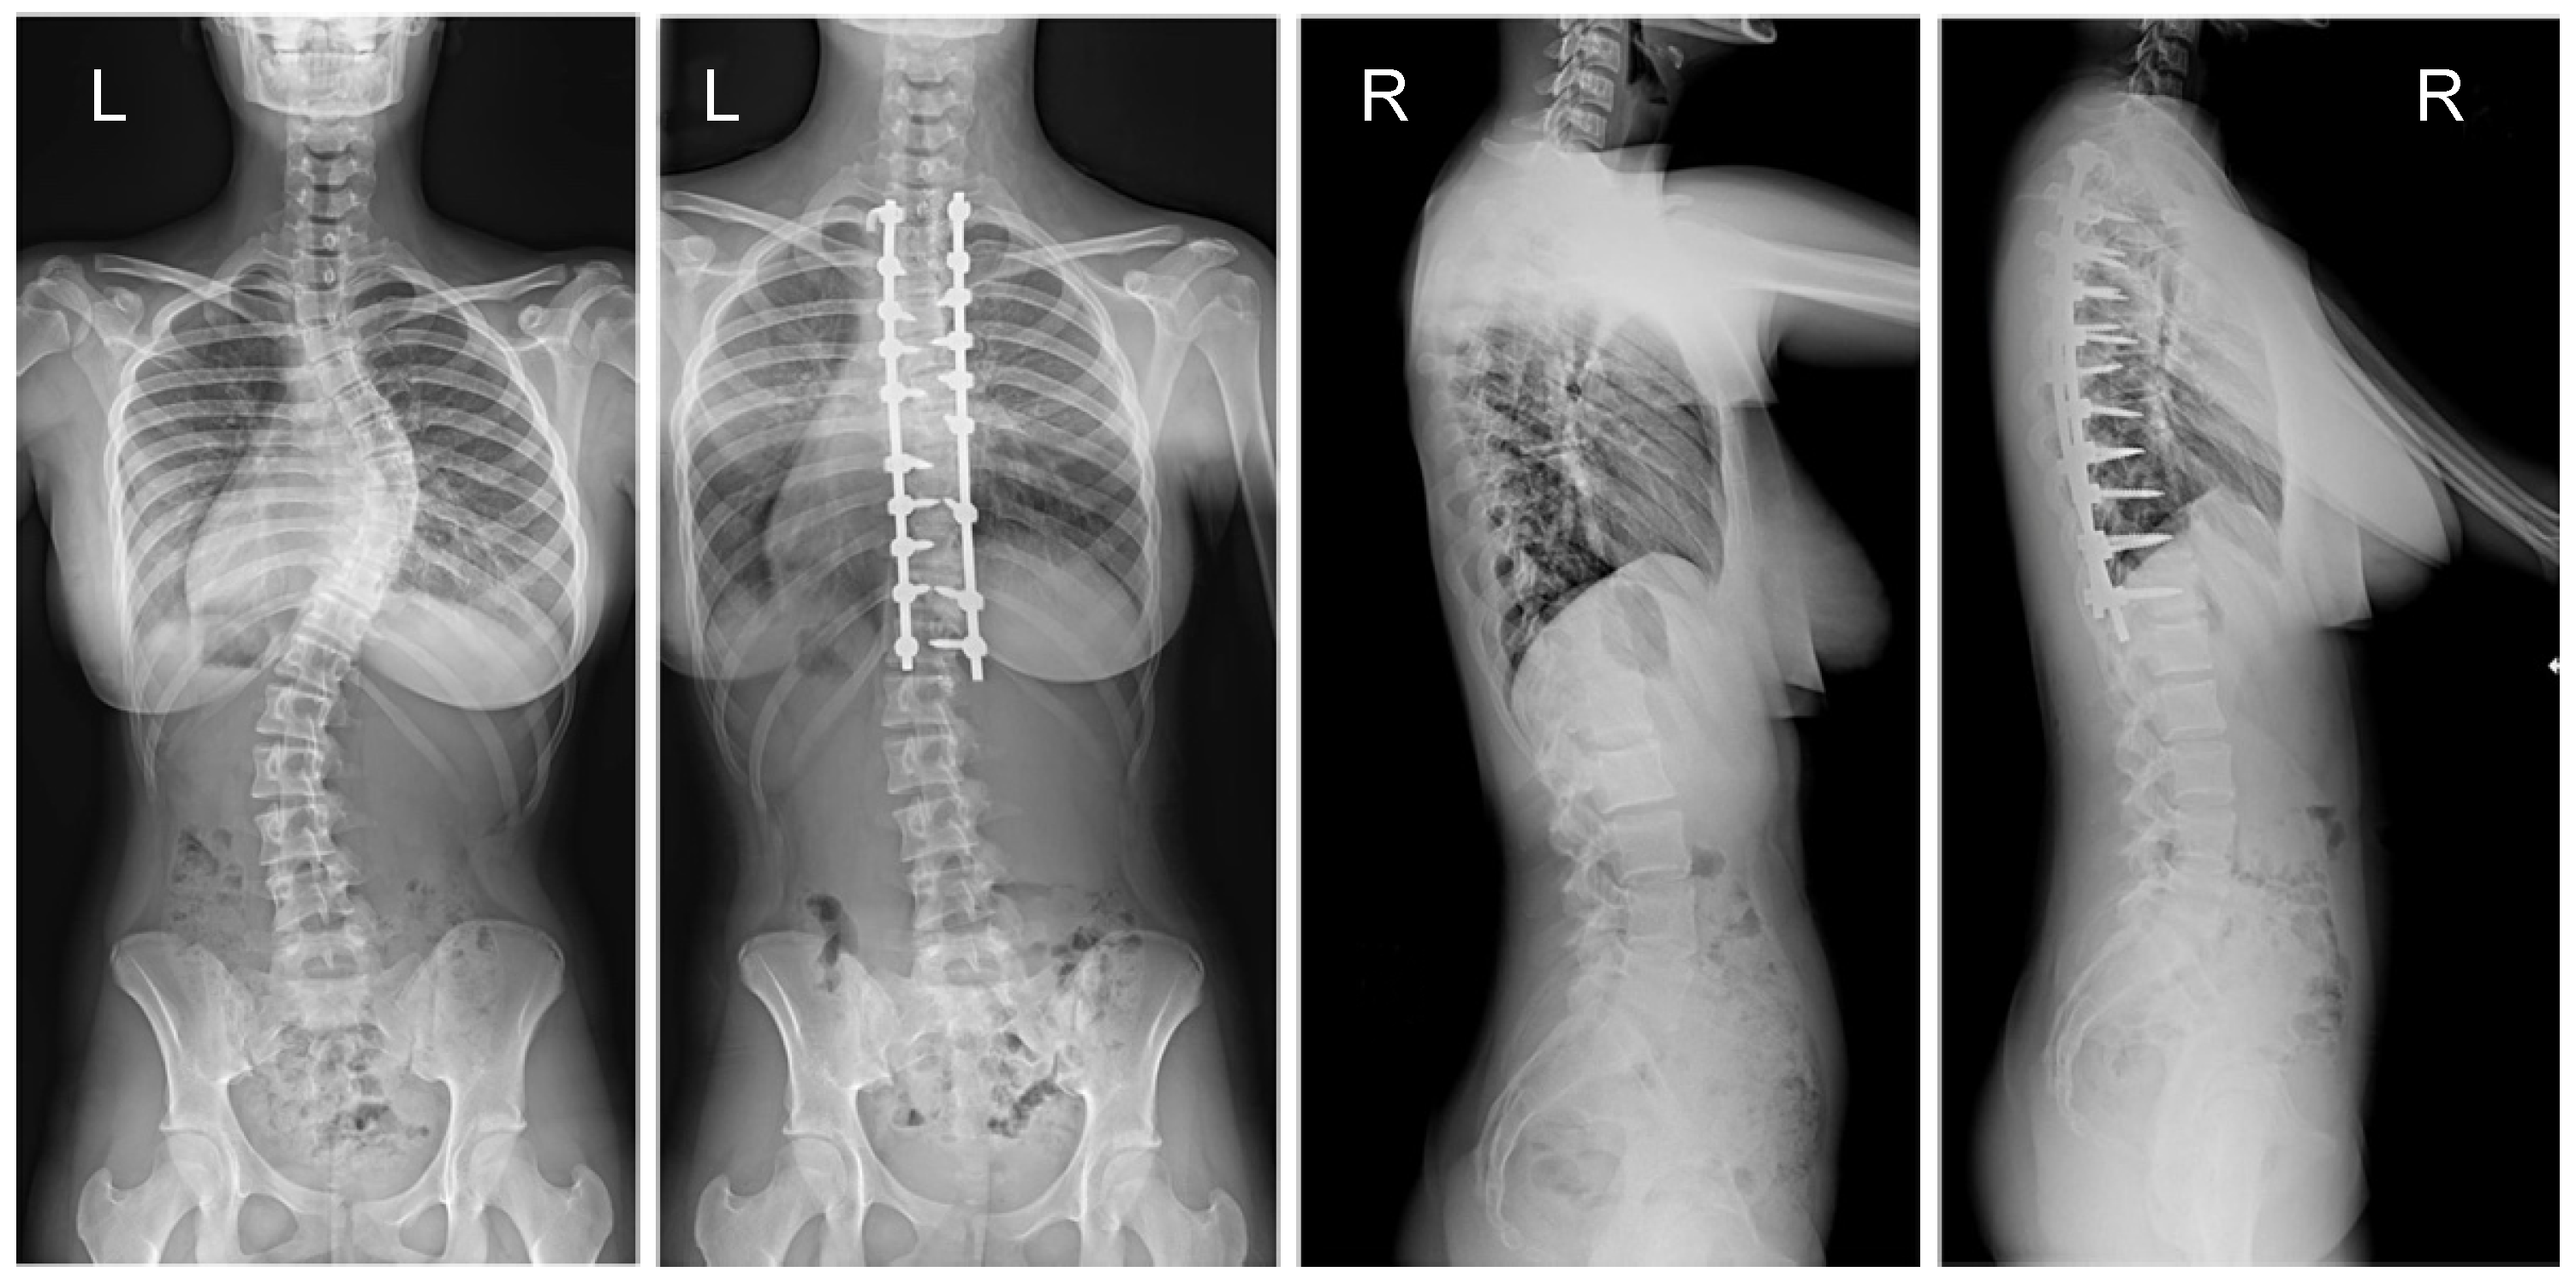

3.1. Clinical Characteristics and Radiographic Outcomes

| Preop major Cobb, degrees | 57.6 (11.9) | 62.5 (12.1) | 0.949 |

| Postop major Cobb | 19.8 (10.2) | 16.6 (8.2) | 0.001 |

| Final follow-up Cobb angle | 21.3 (9.2) | 17.1 (7.2) | 0.001 |

| % Cobb correction, postoperative | 69.8 (12.8) | 74.5 (11.2) | 0.001 |

| % Correction (FFU) | 61% (15) | 68% (14) | 0.001 |

| Flexibility rate | 35% (11) | 33% (8) | 0.382 |

| Ponte osteotomy levels (n) | 5.8 (2.2) | 5.6 (2.5) | 0.978 |

| Preop kyphosis T5–T12 | 25.1 (15.5) | 26.9 (15.8) | 0.779 |

| Postop kyphosis T5–T12 | 24.8 (8.8) | 23.5 (10.8) | 0.012 |

| Final follow-up TK T5–T12 | 25.2 (9.8) | 21.9 (10.2) | 0.001 |